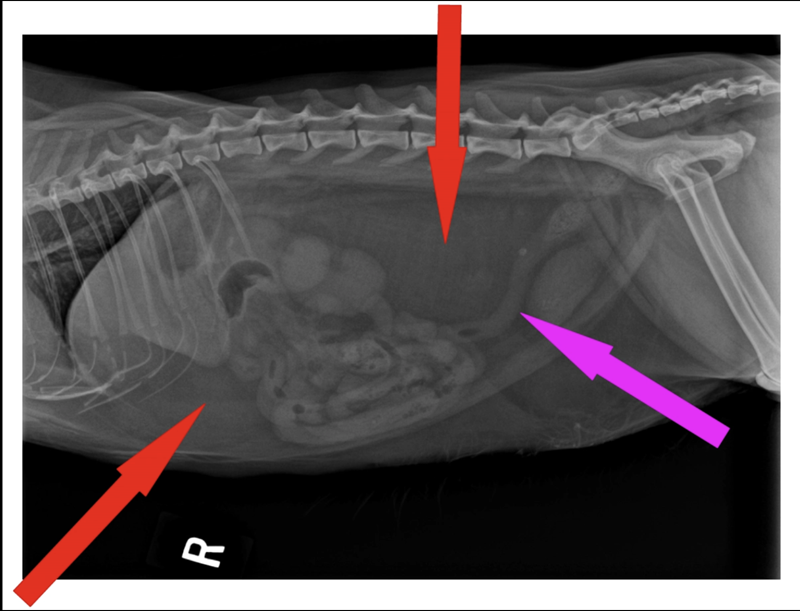

The red arrows indicate two areas of fat pockets (there is more below the pink arrow, however we aren’t as concerned with that for the purpose of this blog). Notice the compression on the stomach, intestines and colon (plus the other organs above and beside those are hard to even see). Also note that the fat pockets will also be pushing into the chest cavity compressing the area available for the heart and lungs.

The pink arrow indicates the colon which has an uphill “S” shape making it so that the body has to work harder to move fecal matter out. This is part of why overweight cats often have issues with constipation.

Looking at this x-ray it may not seem too bad, but let’s compare to a cat that is at a nice lean weight: